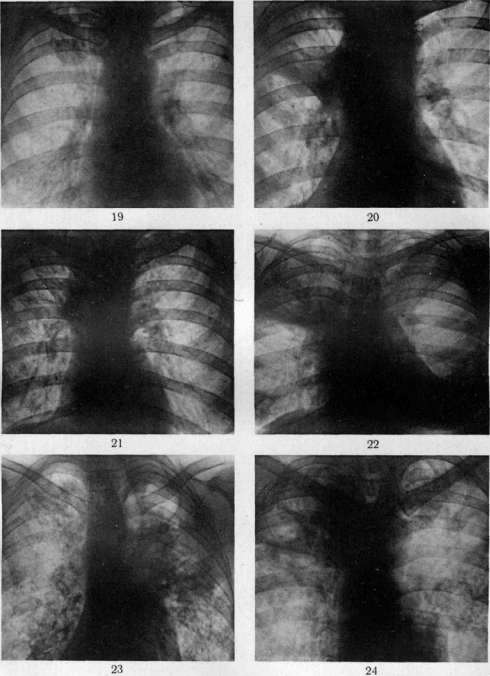

гематогенной генерализацией в результате проникания туб. бацил в ток крови непосредственно или через посредство лимфы (см. Туберкулез). В легких гематогенное поражение проявляется разно. При обшем милиарном Т. в обоих легких наблюдается высыпь массы милиарных туберкулов [см. отд. табл. (ст. 119—120), рис. 3]; в этих случаях ткань легких представляется полнокровной и на таком фоне видны бугорки в зависимости от возраста и типа их или мелкие, серые, полупрозрачные или желтые, с неровными контурами, часто более крупные. Нередко можно, согласно указанию Рибберта (1902), заметить, что у взрослых в верхних районах легких бугорки несколько более крупны, чем в нижних, что объясняют более энергичным ростом туберкулов именно в верхних отделах легких. Если проникание туб. бацил произошло в ветвь легочной артерии, то мидиариза-ция захватывает лишь соответствующую часть легочной территории. Микроскоп, исследование при милиаризации в легких может открыть разный тип бугорков: иногда это типичные продуктивные эпителиоидные бугорки, имеющие своим источником развития альвеолярные перегородки; бугорки растут, сдавливая и уничтожая альвеолы и оставаясь долго продуктивными бугорками; в других случаях к бугорку, начавшему развиваться в альвеолярной перегородке, быстро присоединяется эксудация в альвеолы; наконец бывает так, что бугорок как бы сразу возникает в виде милиарной пневмонии, захватывающей 2—4 соседних альвеолы (милиарный альвеолит), и таким образом обнаруживает экеудативный характер. Гюбшман и Шлейсинг выдвигают ту точку зрения, что всякий бугорок в легких начинается в виде милиарной пневмонии и уже потом окружается продуктивной зоной. Эта точка зрения вызвала категорические возражения крупнейших патологов (Герксгеймер, Ашоф, Штернберг и др.); кроме того Гретман (Grethmann, 1928) установил, что гематогенные милиарные бугорки в легких как правило развиваются в виде продуктивных бугорков из стенок мелких сосудов; эксудация в альвеолы есть явление последовательное, частое, но не обязательное. Гематогенное метастазирование в легкие может еще происходить в виде появления в легких одного или нескольких туб. очагов; по своему существу такая форма есть частное проявление органного T.j возникающего в порядке поздней генерализации первичного Т. (см. Туберкулез). Судьба и выражение таких отдельных гематогенных фокусов в легких бывает разной (см. ниже). Попытка Симона (Simon) объяснить все верхушечные рубцы, встречаемые в легких взрослых, гематогенным метастазированием, происходящим в детстве, у патологов не имела успеха; такое гематогенное метастазирование в верхушку легкого в детском возрасте встречается редко и на детских трупах мы не встречаем ничего похожего на начало образования этих очагов; верхушечные рубцы легких наблюдаются почти только у взрослых, и частота их возрастает с возрастом. Первичный Т. приводит к смерти детей или в связи с значительным распространением туб. процесса в легких или в связи с генерализацией, особенно в виде общего милиарного Т. и туб. менингита, У взрослых первичный Т. легких бывает очень редко; чаще всего это касается тех народностей, к-рые в детском возрасте не соприкасаются с туб. вирусом (см. Туберкулез).—В торичный Т. легких представляет собой то, что принято выделять в качестве легочной чахотки взрослых; по существу это—вспышка туб. процесса, или реинфект в легком у индивидуума, к-рый уже перенес первичную инфекцию и является относительно иммунным к туб. вирусу. Главной особенностью вторичного Т., или реинфекта является то, что процесс протекает б. или м. изолированно в легком, не обнаруживая склонности к лимфогенным и гематогенным метастазам. Если пат. анатомия легочной чахотки взрослых уже давно разработана достаточно хорошо и представляется б. или м. ясной, то этого нельзя сказать относительно патогенеза начальных изменений. В прежнее время, когда еще не делалось различий между Т. детского возраста и Т. взрослых, когда еще не было ничего известно по поводу первичного и вторичного Т., аллергии и пр., казались совершенно очевидными два обстоятельства: 1) легочная чахотка взрослых есть следствие аэрогенной инфекции легкого туб. палочкой; 2) легочная чахотка взрослых всегда начинается в области верхушки легкого. Изучение строения начальных фокусов Т., обнаруживаемых в верхушках, показало (Birch-Hirschfeld,1899; Schmorl,1901), что в них дело идет о туб. поражении стенки апикального бронха и развитии в таком месте бронхита с перибронхитом. Абрикосов (1904) при своих исследованиях начальных туб. очагов верхушек пришел к несколько иному заключению; он нашел, что поражение обычно начинается ниже, именно в районе 2-го дорсального субапикального бронха верхней доли и что фокус имеет бронхопневмонический характер. Абрикосов высказался за то, что процесс начинается со стенки внутридольковой бронхиолы и быстро принимает бронхопневмонический характер. Эти исследования подвели как бы фактический фундамент под теорию аэрогенного происхождения легочной чахотки; отчасти в связи с этим взгляды Ауфрехта (Aufrecht, 1900) и Рибберта (1901) о гематогенном происхождении легочного Т. взрослых не имели никакого успеха. После того как выдвинулось положение о патогенетическом отличии Т. детского возраста и Т. взрослых и сущность этого отличия была разъяснена в учении Ранке (см. Туберкулез), стало очевидным, что так просто смотреть на генез легочной чахотки взрослых, как это делалось раньше, нельзя. Раз оказалось, что легочная чахотка взрослых есть Т. организма, уже перенесшего туб. инфекцию, то естественно стали говорить, что в основе Т. взрослых лежит вторая инфекция, или реинфекция туб. вирусом. Механизм этой реинфекции понимался различно. По учению Ранке, реинфекция представляет собой не что иное, как обострение-изменений, относящихся к первичному Т. детского возраста (эндогенная реинфекция); т. о. Т. взрослых есть продолжение Т., идущего с детского возраста, но обостряющегося у взрослого, находящегося в состоянии относительного иммунитета к туб. вирусу. В противоположность этому Ашоф и др. стали настаивать на том, что легочная чахотка взрослых в громадном большинстве случаев есть следствие новой аэрогенной инфекции легкого, т. е.— экзогенная реинфекция или суперинфекция организма, уже перенесшего первичную.инфекцию. В последние годы очень многие фтизиатры склонились к мнению, что легочная ча- хотка взрослых есть следствие эндогенной реин-фекции по гематогенному пути. Источником такого гематогенного метастазирования в легкое являются или очаги первичного комплекса в легком и в лимф, железе средостения или туб. фокус в каком-нибудь органе, развившийся в порядке органного туберкулеза. Другой спорный пункт, выявившийся в последние годы, касается места начала легочной чахотки взрослых. До 1925 г. учение о том, что легочная чахотка начинается с самой верхушки легкого к что встречающиеся в верхушках рубцы с петрификатами и без них являются как раз выражением такого начала, не получившего в дальнейшем развития (зажившие очаги реинфекта), казалось совершенно незыблемым. В 1925 г. Асман (Assmann), в 1926 г. Редекер (Redeker), а в ближайшее время Ульрици, Ромберг, Лидтин (Romberg, Lydtin) и мн. др. на основании клинических и рентгенологических данных стали настаивать на том, что вышеуказанные верхушечные очаги никакого отношения к началу легочной чахотки не имеют, что легочная чахотка начинается не в верхушке, а в той области верхней доли, к-рая проецируется непосредственно ниже ключицы; как раз здесь начинается процесс в виде очага пневмонии, что и было обозначено как и н -ф р а к л а в и к у л я р н ы й (подключичный) инфил ьтрат или ранний ту б. инфильтрат (нем. Fruhinfiltrat). С такой точкой зрения не могли согласиться патологоанатомы (Ашоф, Graff, Гюбшман, Loeschke и др.), которые утверждали, что инфракдавикудярный инфильтрат не есть анат. начало легочной чахотки, а лишь клинико-рентгенологическое выявление процесса, начавшегося в верхушке и протекавшего до того без ясных клин, симптомов. На специальном туб. конгрессе в Вильд-баде (1928) и на съезде патологов в Вене (1929) это противоречие еще не было устранено. Однако в самое последнее время мы видим значительное смягчение указанного спора, связанное с тем обстоятельством, что, с одной стороны, патологоанатомы (Ашоф, Штернберг, Pa-gel, Schtirmann и др.) склонились к допущению возможности начала туб. процесса у взрослых с подключичной области, а с другой стороны, и клиницисты (Лидтин, Асман, Star linger, Рубинштейн и др.) согласились с тем, что инфракдавикулярный инфильтрат вовсе не обязательно является самостоятельным начальным фокусом Т., он может развиваться и последовательно из предсуществовавшего лятентного очага. Одновременно стали определенно говорить, что реинфект, являющийся началом легочной чахотки взрослых, может иметь как эндогенное, так и экзогенное происхождение. Т. о. в наст, время допускаются разные способы происхождения легочной чахотки взрослых и разные типы ее начала. Происхождение ее может быть в результате экзогенной (аэрогенной) и эндогенной реинфекции; эндогенная реинфекция развивается гематогенно или непосредственно из старого очага в легком (по соприкосновению иди бронхогенно). В смысле своего начала процесс может исходить из верхушечных очагов иди начаться в подключичной области. К этому надо еще прибавить возможность развития легочной чахотки взрослых из туб. лимф, желез ворот легкого. Последний способ образования реинфекта в легком является однако сравнительно редким; поэтому практическое значение имеют два спо- соба начала легочной чахотки: из верхушки легкого и из подключичной области его. С этим в наст, время согласно большинство патологов и клиницистов (Ашоф, Pagel, Schilrmann, Асман, Лидтин, Рубинштейн, Угрюмов, Штеф-ко и др.). Однако нет еще полного согласия в том, какой способ начала является более частым; у клиницистов имеется склонность считать инфраклавикулярное начало более обычным и указывать, что верхушечное начало наблюдается, лишь в 7—1Q% случаев Т. (Ромберг). С другой стороны, патологоанатомы на основании секционного материала устанавливают, что случаи с верхушечным началом относятся к случаям с подключичным началом, как 4 : 1 (Pagel, Угрюмов), т. е., что начало с верхушки легкого в 4 раза чаще, чем начало с инфракла-викулярной области. Совершенно открытым считается вопрос о том, насколько часто аэрогенное (экзогенное) и насколько часто гематогенное (а также другого типа эндогенаое) развитие реинфекта. Большинство указывает, что инфракдавикудярный очаг имеет гематогенное происхождение, тогда как верхушечные очаги могут иметь аэрогенное и гематогенное происхождение. В противоположность этому Нейман и Штарлингер (Neumann, Star linger) считают, что как раз ранний инфракдавикудярный инфильтрат есть результат аэрогенной (бронхогенной) суперинфекции, тогда как верхушечные очаги имеют гл. обр. гематогенное происхождение. Оставляя в стороне эти еще неясные и спорные пункты генеза легочной чахотки, коснемся пат. анатомии: 1) верхушечных очагов и 2) ин-фраклавикулярных инфильтратов. 1. Понятие «верхушка легкого» не у всех авторов одинаково; одни под «верхушкой» понимают лишь самый купол верхушки (нем. Кирре), другие—верхнюю треть верхней доли. Разное понимание является одной из причин несогласного толкования у авторов локализации верхушечных очагов. Надо заметить, что у взрослых предрасположенной к Т. является вся верхняя треть верхней доли легкого, в к-рой и встречаются верхушечные очаги реинфекта. Предрасположение этой верхней части легкого к Т. по современным воззрениям (Ors6s, Loeschke) связано с тем, что на ней наиболее сильно сказывается влияние тяги диафрагмы, создающей здесь малокровие и ателектатическое состояние легочной ткани вследствие сдавления сосудов и бронхов; это проявляется особенно сильно у лиц с астенической грудной клеткой. Относительно числа и локализации верхушечных реинфектов наиболее точные данные представляются Шюрма-ном: в 40,8% всех реинфектов обнаружен 1 очаг, в 26,4%—2—4 очага, в 23,2%—5—10 очагов, в 9,6%—более 10 очагов. Множественные реин-фекты могут иметь одинаковый возраст, что говорит за одновременное их образование, или же представляют разную степень развития, что свидетельствует о разном сроке их возникновения и м. б. зависимости друг от друга. В 37,4% реинфекты имелись только в правом легком, в 30,1% — только в левом, в 32,5%—в обоих легких. В 40% очаги лежали в самом куполе верхушки, в 60% пальца на два ниже купола (Абрикосов также находил, что начальные очаги обычно лежат не в самом куполе, а в районе субапикального бронха). По Стру-кову 00,4% очагов встречаются в правом легком, 23,2%—в левом, 16,4%—в обоих легких. Х17 Внешний вид верхушечных очагов может быть разным. Размеры их колеблются от 2 до 15 мм в диаметре. Иногда очаг представляет собой просто ограниченное утолщение плевры, на разрезе к-рого обнаруживается слой плотной хрящеподобной соединительной ткани без каких-либо творожистых гнезд и петрификатов, в других случаях это — антракотический очаг, тоже располагающийся плеврально, далее идут втянутые рубцы, связанные с плеврой и сопровождающиеся образованием синехий между париетальной и висцеральной плеврой; они могут быть без петрификатов или с ними; наконец часто встречаются казеозные и петри-фицированные очаги, расположенные в отдалении от поверхности и находящиеся в связи с плеврой или лежащие свободно в легочной ткани без связи с плеврой. Имеется склонность (Штефко) подразделять эти очаги на: 1) интра-пульмоналыгые и 2) плевропулъмональные (экстрапудьмональные, плевральные) с подразделением интрапульмональных очагов (Стру-ков) на: а) классические верхушечные реинфек-ты(аэрогенные) и б) очаги Пуля (гематогенные). Другие, выключая плевральные очаги как не-слецифические, рассматривают отдельно Симоновские и Пулевские очаги и т. д. Описания этих отдельных типов верхушечных очагов и их квалификация далеко не совпадают у разных авторов, что заставляет считать вышеуказанные классификации, точно так же как определение одних очагов как гематогенных, других—как аэрогенных, весьма субъективными и шаткими. Если плевральные утолщения и антракотические узелки без казеоза и петрификатов не считать относящимися к Т., то получается, что реинфекты встречаются в 50— 60% всех трупов взрослых; если же квалифицировать как tbc также и плевральные утолщения, рубчики, антракотические узелкрг (как это делают Ашоф, Focke, Anders и др.), то оказывается, что очаги реинфекта встречаются на трупах взрослых не реже, чем первичный аффект, т. е. в 95—98%. По современным воззрениям всякий реин-фект в самом начале его развития представляется в виде очага «раннего инфильтрата», т. е. пневмонического фокуса с весьма слабыми про-лиферативными явлениями; это конечно еще не исключает того, что и до вспышки пневмонического процесса в стенке бронхиолы имелся туб. очажок, к-рый и является началом всего процесса. Очаг пневмонии может подвергнуться обратному развитию, рассасыванию, чаще однако он претерпевает творожистое перерождение и инкапсуляцию. Инкапсулированные очаги реинфекта, Пулевские или Ашоф-Пулев-ские очаги, как их называют (в противоположность Гоновским очагам первичного аффекта), очень полиморфны по своему виду; они то круглы, то овальны, то состоят из группы отдельных узелков, нередко ориентированных по разветвлениям мелкого бронха; особенностью их является нерезко выраженная и сравнительно поздняя петрификация, отсутствие образования в капсуле костной ткани, толстая неспецифическая капсула с углем и с распространением соединительнотканного разрастания с лимфоидными скоплениями на соседнюю легочную ткань; нередко образование соединительнотканных тяжей, связывающих капсулу с плеврой, с сосудами и бронхами. Иногда вокруг очага легочная ткань па большом протяжении ателектатична, склерозирована, ан- тракотична, с бронхоэктазами. Как показывает бактериол. исследование инкапсулированных и петрифицированных очагов реинфекта, в них долго содержатся вирулентные туб. бацилы. Кроме того и микроскоп, исследование нередко вокруг таких казалось бы совершенно заживших очагов открывает свежие бугорки. Поражения регионарных лимф, желез при реинфек-тах не бывает; иногда в железах наблюдаются лишь отдельные бугорки. Как уже указано, в наст, время взгляд, что верхушечные реинфекты могут быть источником легочной чахотки, т. е. прогрессирующего Т., является общепринятым. Развитие туб. процесса из верхушечных очагов происходит 4 способами: 1) иногда образовавшийся реинфект непосредственно увеличивается и образует крупный пневмонический очаг (верхушечный инфильтрат), к-рый в дальнейшем прогрессирует; 2) в других случаях рядом с как бы зажившим реинфектом по соприкосновению появляются свежие бугорки и очаги пневмонического типа; 3) очаг реинфекта, расположенный у стенки бронха, дает прорыв в бронх и развитие бронхогенных метастазов как вблизи, так и в отдалении от очага; 4) из реинфекта процесс распространяется лим-фогенно по ходу бронха, давая туб. периброн-хит, а в дальнейшем и туб. бронхит с бронхо-гешгой диссеминацией. Лешке считает эти два последних пути самыми частыми типами начала легочной чахотки взрослых и даже инфракла-викулярный инфильтрат квалифицирует как бронхогенный метастаз из верхушечного реинфекта. 2. Инфраклавикулярный ранний инфильтрат с патологоанатомической стороны описан небольшим числом авторов (Асман, Zadek, Schurmann, Pagel, Штефко, Рубинштейн и Пожариский, Угрюмо в); зависит это от того, что в периоде раннего инфильтрата больные не умирают, вследствие чего ранний инфильтрат в большинстве случаев можно уловить на секционном столе лишь в качестве случайной находки у б-ных, умерших от других б-ней. Анатомически инфраклавикулярный инфильтрат представляет очаг острой се-розно-фибринозной пневмонии с колятераль-ным отеком; такой очаг может в дальнейшем рассосаться, оставив после себя лишь небольшой склероз легочной ткани, или же подвергается творожистому перерождению, представляя в этом случае однородное казеозное поле величиной в 2—3 см в диаметре; казеозный очаг может инкапсулироваться и петрифициро-ваться; однако нередко происходит размягчение творожистой массы и выделение распада через бронх, что ведет к образованию полости с казеозными изрытыми стенками, называемой ранней каверной. По периферии основного очага инфильтрата нередко наблюдается ряд более мелких очагов такого же строения и с тем же течением. Распад очага и сообщение его с бронхом являются предпосылкой к прогрессирующему распространению Т., т. е. развитию легочной чахотки. Происхождение ин-фраклавикулярных инфильтратов повидимому не всегда бывает одинаковым. Нет никакого сомнения в том, что они могут возникать как самостоятельный реинфект, вероятно гематогенного (по Штарлингеру—аэрогенного) происхождения; с другой стороны, нельзя отрицать возможности развития их из более старых реинфектов, к-рые могут располагаться вблизи инфраклавикудярного района (Абрикосов, Шюрман, Ашоф), или даже из верхушечных ре-инфектов в духе взгляда Лешке. Указывается еще возможность образования инфраклавику-лярных инфильтратов по ретроградному току лимфы из бронхиальных лимф, желез, пораженных Т. Если инфраклавикулярный инфильтрат может иметь разное происхождение, то естественно возникает мысль о том, что подключичная область легкого представляется особо предрасположенной к вспышке здесь туб. пневмонии при разных путях проникновения туб. вируса. Более редкими типами начала легочной чахотки надо считать следующие. 3. Многие выделяют еще в качестве особого вида начальных изменений при легочной чахотке гематогенную форму начала. В качестве признаков этой формы, кроме наличия где-нибудь в организме очага, могущего дать гематогенные метастазы, указываются: множественные, равномерно распределенные в верхушке легкого мелкие фокусы или множественные небольшие однородные каверны среди ин-дурированной иди эмфизематозной ткани; эти очаги обладают сравнительно небольшой наклонностью к распространению, особенно брон-хогенному. 4. Реинфект из туб. лимфатических желез ворот легких происходит в тех случаях, когда после ликвидации первичного аффекта в легком процесс в регионарной лимф, железе или в группе желез продолжает существовать в лятентном состоянии; в легком в таких случаях может вспыхнуть процесс по соприкосновению непосредственно в примыкающей легочной ткани в виде гилюсного инфильтрата, или же происходит ретроградное распространение внутрь легкого по лимф, путям, или наконец процесс с лимф, железы переходит на стенку бронха и дает бронхогенные метастазы, как это бывает в периоде первичного туберкулеза. Процесс, начавшийся по одному из вышеуказанных четырех способов (чаще по способу 1 или 2), распространяется частью по соприкосновению, частью по воздухоносным путям легкого, т. е. интраканаликулярно, бронхогенно. Как правило при легочной чахотке взрослых распространение туб. процесса, начавшегося в верхнем отделе легкого, идет в направлении сверху вниз; поэтому в верхних отделах имеются более старые изменения и, чем ниже, тем изменения являются более свежими. Характер всех этих изменений соответствует тому, что указано выше о пат. анатомии Т. вообще (см. Туберкулез). Распространение из места начала процесса по соприкосновению выражается или в том, что зона пневмонических (эксудативных) изменений быстро расширяется, подвергается казеозу, распаду [см. отд. табл. (ст. 119—120), рис. 4, и отд. табл. (ст. 111—112), рис. 5] с образованием одной или нескольких полостей—каверн (см.), или, если первоначальный очаг был окружен зоной специфической грануляционной ткани и бугорками, происходит преимущественно продуктивное, сравнительно медленное разрастание этой грануляционной ткани и развитие новых бугорков с сдавливанием и уничтожением альвеол и слабыми пневмоническими (эксудативными) проявлениями. В дальнейшем указанные грануляционные разрастания [см. отд. табл. (ст. 35— 36), рис. 1] могут подвергнуться казеозу, распаду или же обнаруживают склонность к фиброзному превращению, сопровождаясь неред- ко развитием вокруг неспецифической соединительной ткани. Бронхогенное распространение при легочной чахотке взрослых имеет доминирующее значение. При нарушении целости бронха в районе начального фокуса или в связи с уже имеющимся сообщением с просветом бронха в виду бронхопневмонического строения очага творожистые массы, содержащие туб. ба-цилы, при дыхательных движениях передвигаются в просвете бронха и аспирационно заносятся в новые разветвления бронхиального дерева. В результате заноса инфекционного материала в мелкие бронхи—бронхиолы—вспыхивают преимущественно эксудативные очаги туб. пневмонии, соответствующие той части дольки, к-рая носит название ацинуса; их называют ацинозными очагами; они имеют вид желтовато-серых, угловатых очагов размерами ок. 2 лиц в диаметре («мелкое зерно» рентгенологов). Аци-нозный фокус, имея вначале пневмонический характер, может в дальнейшем сохранять таковой и увеличиваться, захватывая соседние ацинусы и давая в конце-концов более крупный лобулярный (дольковый) пневмонический фокус. Лобулярный фокус может образоваться и сразу как таковой при распределении инфекционного материала сразу по всем ветвям лобулярного бронха. Лобулярный очаг имеет вид казеозного фокуса с фестончатым краем; размер его около 1,5 см в диаметре («крупное зерно» рентгенологов). С другой стороны, ацинозный очаг может в самом начале получить грануляционную зону, ограничивающую его распространение и придающую ему преимущественно продуктивный характер. Группа рядом расположенных таких ациноз-ных очагов с продуктивной зоной дает т. н. ацинозно-нодозный фокус [см. отд. табл. (ст. 119—120), рис. 1, верхушка легкого— см. нижнюю часть рисунка]; обычно фокус име-ет центральную часть, состоящую из ателек-татической, богатой угольным пигментом легочной ткани, и периферию из ряда продуктивных ацинозных очагов; размер ацинозно-но-дозного фокуса около 1,5 &м в диаметре («крупное зерно» рентгенологов). Как дольковые пневмонические, так и ацинозно-нодозные фокусы могут сливаться друг с другом, в результате чего образуются поля разных размеров эксу-дативного или преимущественно казеозно-пнев-монического характера или преимущественно продуктивные, состоящие из узелков разных размеров, в центре казеоэных, по периферии— грануляционных и нередко даже с фиброзом; Иногда при легочной чахотке происходит вспышка пневмонического процесса, захватывающего сразу целую долю легкого (л о б а р -ная туб. пневмония). В таких случаях вся доля (обычно нижняя) представляется увеличенной, плотной, со стороны плевры серой; на разрезе в начале процесса ткань нижней доли однородно серого вида; под микроскопом картина катарально-фибринозной пневмонии с большим участием пролиферирующих и десква-мирующихся клеток альвеолярного эпителия (по мнению нек-рых исследователей часть этих клеток относится не к эпителию, а к макро-фагам, выходящим из соединительной ткани альвеолярных перегородок). При видном участии в эксудате альвеолярного эпителия говорят о десквамативной, Булевской туб. пневмонии. Есть данные, говорящие за то, что туб. пневмонии, даже лобарные, не подвергаю-

Plic, 1. Линии ню-ипдопииП, uitpcvririeeuiifi Ll>c легкого t клисрнлмн: n ракушке iiv-4 Mkiiujjuii.it творожистые м.-^си. 1'kCf % АщшовошЙ Ll?c легкого. Рис 3. .""■ "i ■ ■ - -1 - - ■ - -iiiji'i Иpc легкого. Рисунок А. Эксчтштирш.ift iEtc нижней доли легкого; hhoiйчн^шние K..ii!--|'FMJ мiiktic11 доли. Рве. ?>. 1к'|'пич1ил1 туб. комплекс: иолп^СЕнтльнми ТВОРОЖИСТЫМ фокус ЛЕГКОГО II pLTHOHil[4INn ЛНМфалеИНТ; МНЛНОрниЧ IOC UOrjHX JWULL